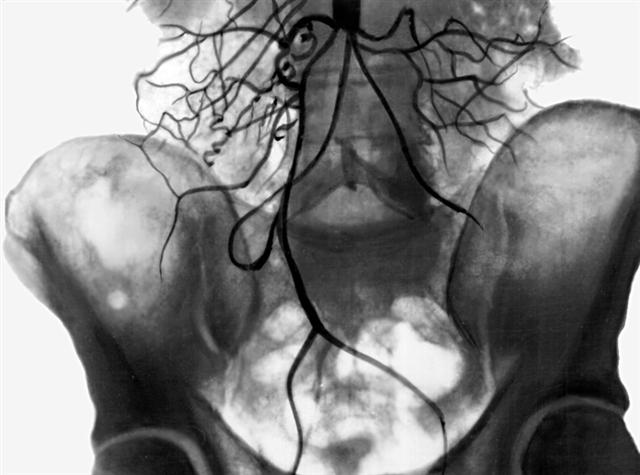

Рис. 3. Аортограмма при высокой окклюзии брюшной части аорты: видны многочисленные коллатерали, берущие начало выше уровня окклюзии аорты.